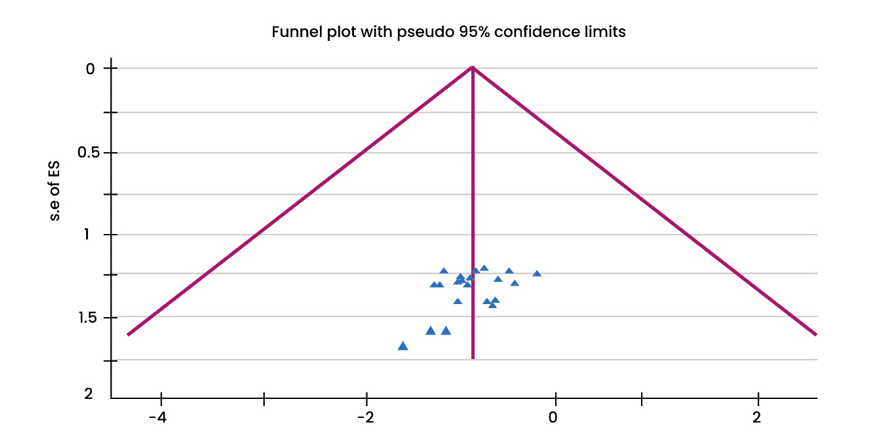

Systematic Literature Review and Meta-Analysis of Timely Initiation of Antenatal Care Among Pregnant Women in Ethiopia: Prevalence and Associated Factors

Background: Timely initiation of antenatal care (ANC) is crucial for clinical practices, including routine hypertension screening, fetal heart sound detection,...Read More